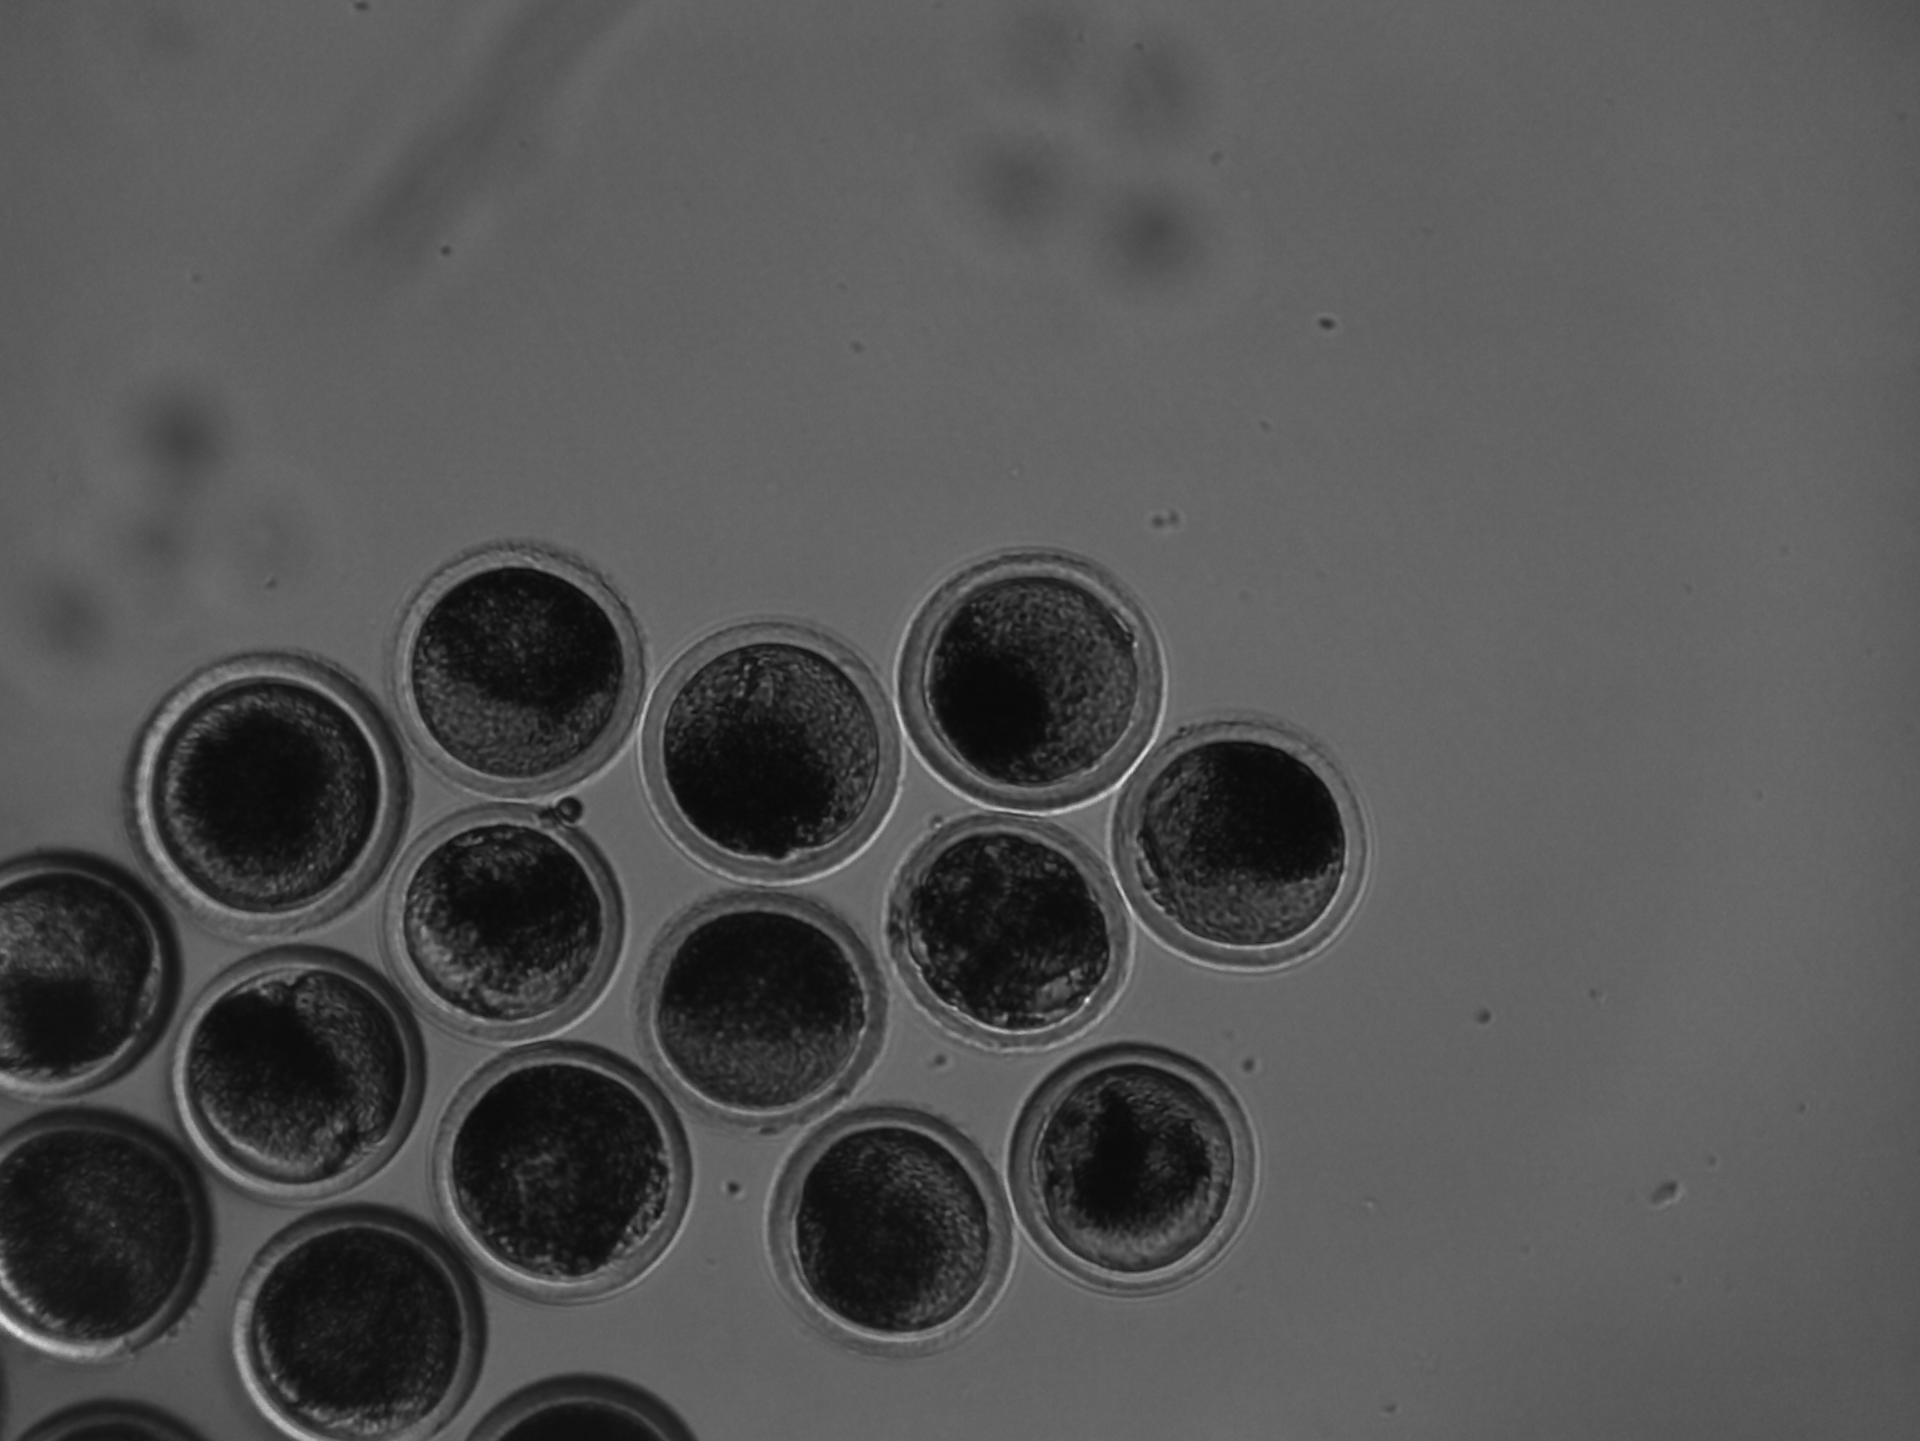

In-vitro-Fertilisation

Die kontinuierliche Überwachung von Proben im Inkubator nach der IVF bietet den Vorteil, das Kontaminationsrisiko zu verringern und gleichzeitig die Embryonenqualität zu verbessern. Dieser optimierte Prozess senkt nicht nur die Kosten, sondern erhöht auch die Erfolgswahrscheinlichkeit und Reproduzierbarkeit, indem hochwertige Proben und stabile Wachstumsbedingungen aufrechterhalten werden.

Kontrolle des Zellwachstums behalten und Wachstumsbedingungen stabilisieren

Die owl bleibt im Inkubator, sodass die Umgebungsbedingungen für Ihre Proben stabil bleiben. Kein Öffnen der Tür für manuelle Kontrollen, keine Temperaturabfälle, keine CO₂-Schwankungen.